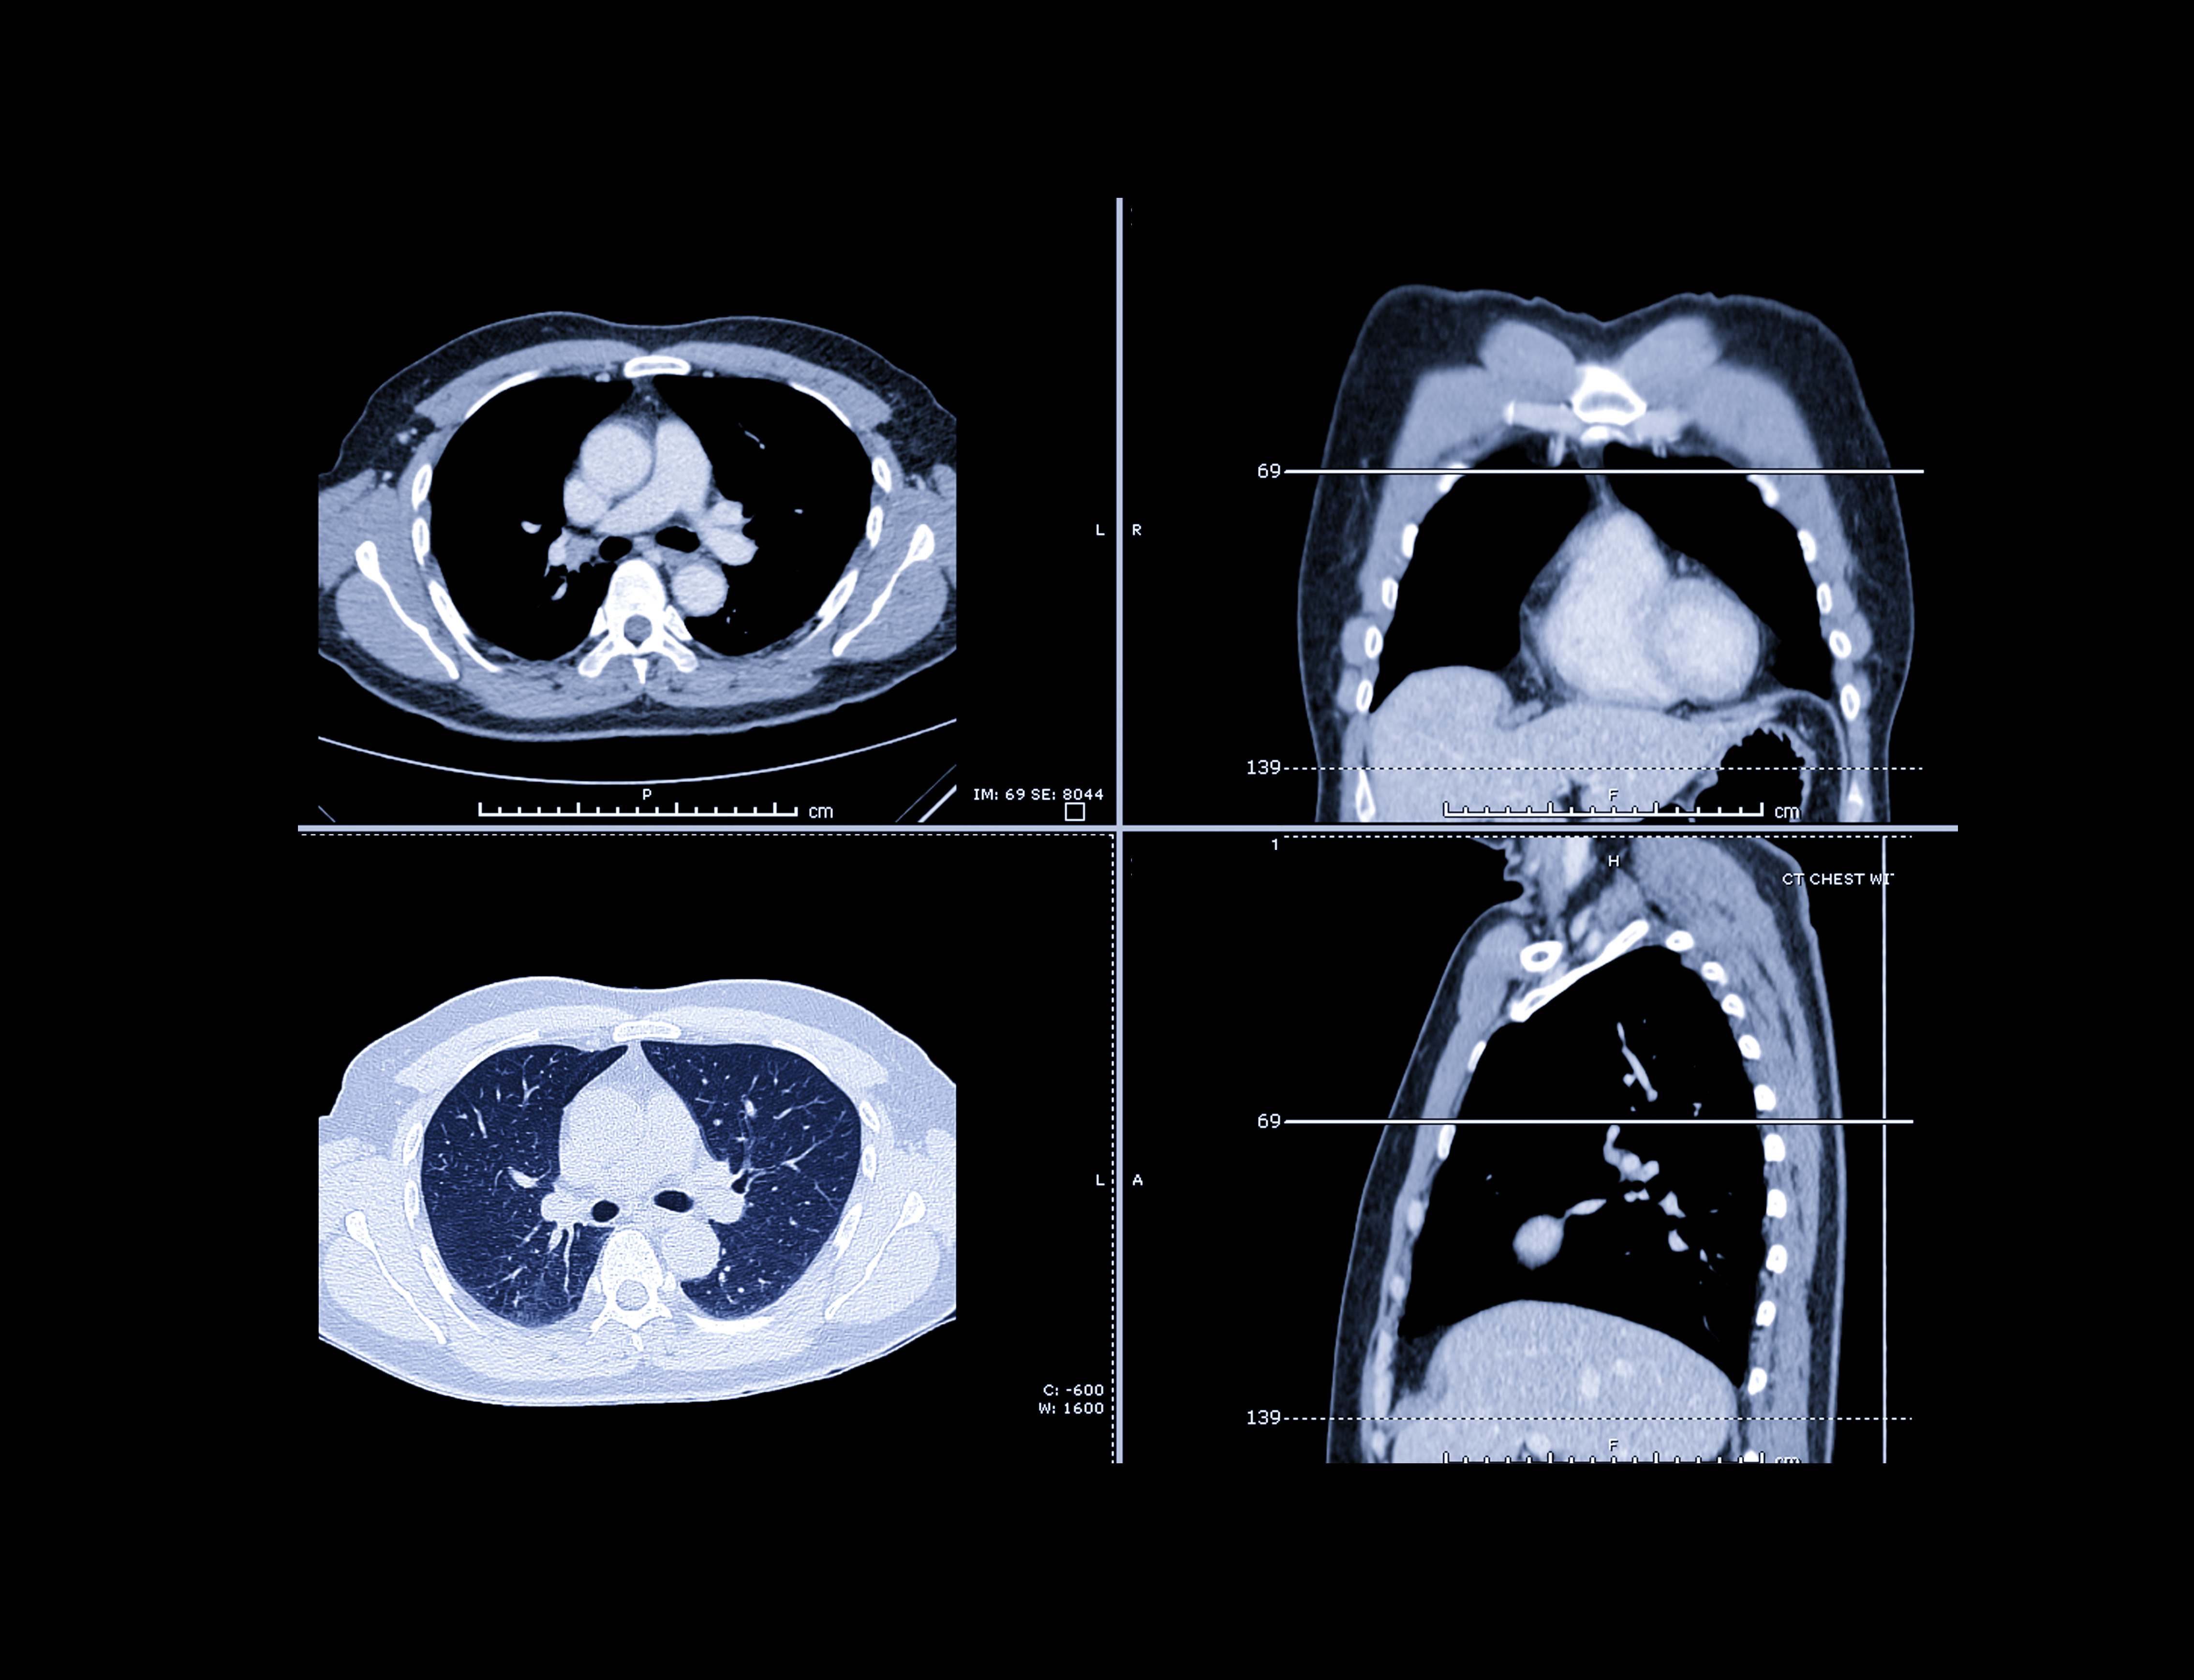

The participants fasted overnight and then underwent dual-energy x-ray absorptiometry (DEXA) and CT scans to determine body composition, as well as MR spectroscopy (MRS) for fat quantification and analysis.